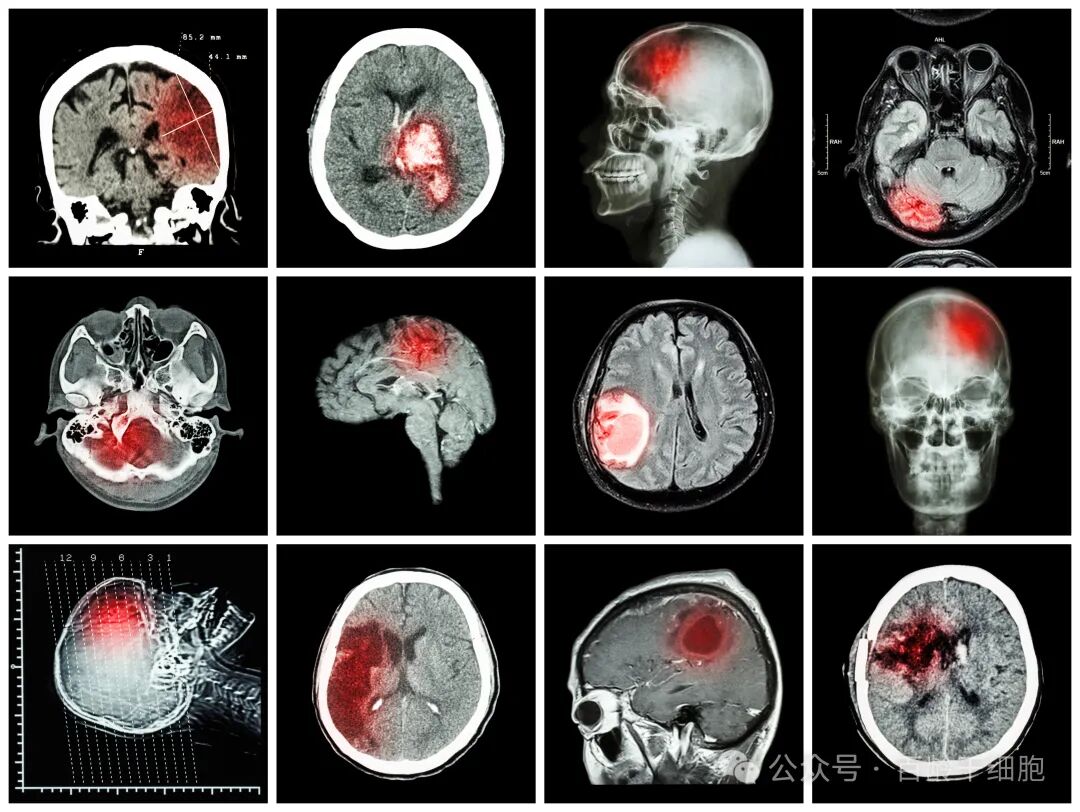

脑出血是一种凶险的卒中类型,约占所有卒中的10%-20%。它不仅死亡率高,幸存者也常面临严重的运动、认知障碍等后遗症,而目前临床治疗对长期功能恢复的帮助较为有限。近年来,干细胞疗法为神经系统损伤的修复带来了新希望。其中,源于新生儿脐带的间充质干细胞(hUCMSC)因其易于获取、增殖能力强、具有神经保护和免疫调节潜能,备受研究者关注。

2026年1月9日,一项发表在《Translational Stroke Research》杂志上的动物研究,为这种疗法提供了新的科学证据。该研究探索了通过静脉注射脐带间充质干细胞,治疗实验性脑出血的效果及其作用机制。